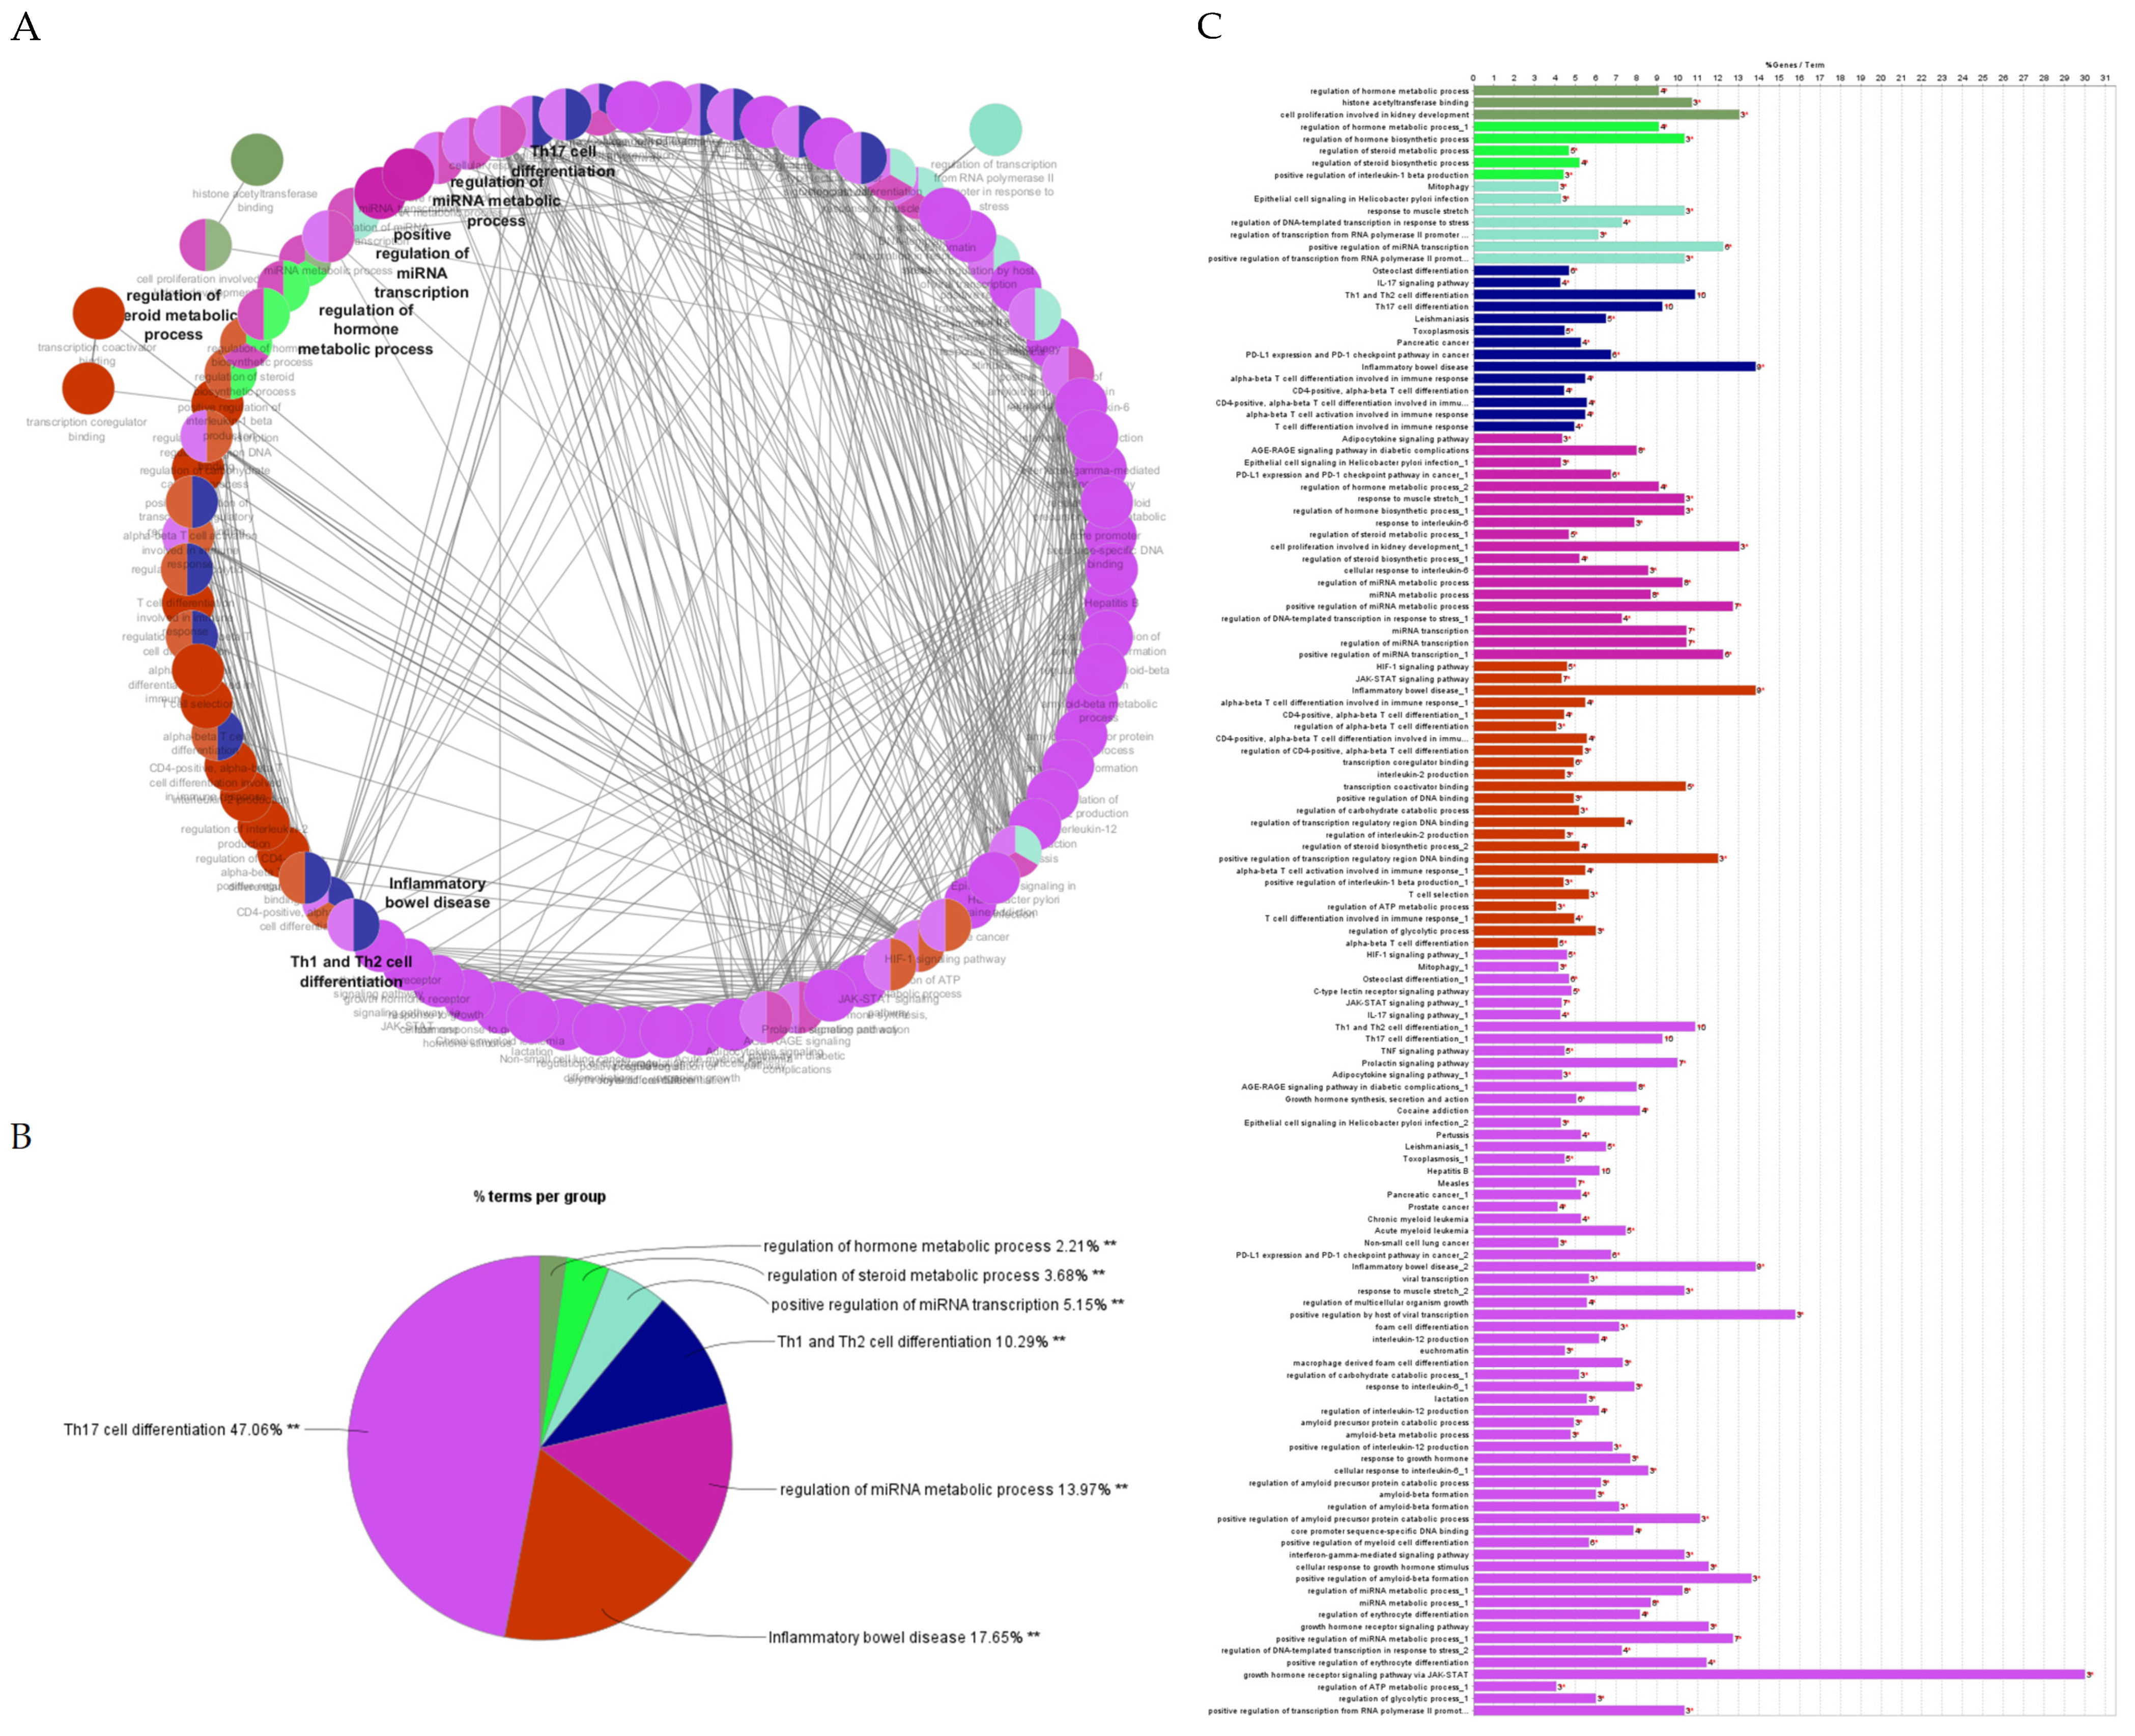

2.4.3. Gene Ontology Enrichment and KEGG Pathway Analysis

2.4.4. Identification and Analysis of Hub Gene

2.4.5. Gene Ontology and Functional Annotation Analysis of Hub Genes